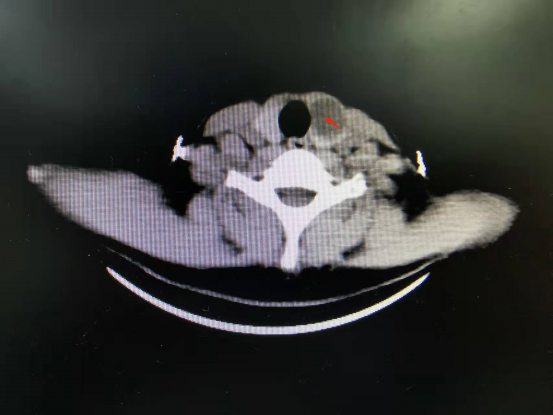

甲状腺结节是甲状腺内肿物的统称,多见于中青年女性。甲状腺结节分为良性和恶性两大类,大部分患者需要手术治疗。传统手术要在患者颈部切口,术后患者颈部会留下明显的手术疤痕,给患者造成很大的心理负担。随着腔镜技术的发展,术者对许多患者不再采用传统的开刀方式,而是采用非颈部入路,将颈部切口改为在胸前很低的乳晕位置开3个0.5厘米~1.0厘米的小孔,完成手术,有很好的美容效果,受到了患者的喜爱。 病例 董某,女,29岁,身高160厘米,体重50公斤。 主诉:发现颈前肿大1天。 现病史:患者1天前无明显诱因出现颈前肿大,无压痛、胀痛,无声音嘶哑,无呼吸困难等;彩超检查结果提示甲状腺结节,较大者约为24.4毫米×17毫米。为了寻求系统治疗,患者来到河南中医药大学第一附属医院就诊。患者神志清醒,精神尚可,颈前肿大,平时易怒,纳可,睡眠一般,二便尚可。 既往史:平素身体状况良好,无冠心病、高血压病、糖尿病、脑梗死、脑出血、肺结核病史。患者说自己没有肝炎,没有手术史、输血史。 一般情况:体温36.6摄氏度,脉搏70次/分,呼吸19次/分,血压113/75毫米汞柱(1毫米汞柱=133.322帕)。 查体:颈软,无抵抗感,双侧颈动脉无异常搏动,颈静脉未见异常,气管居中,肝颈静脉回流征为阴性;甲状腺左叶Ⅰ度肿大,边界尚清,质中等,活动度欠佳,甲状腺右叶未触及异常,双侧未触及明显肿大淋巴结。 甲状腺功能:促甲状腺激素为3.73国际单位/升,甲状腺过氧化物酶抗体为0.6国际单位/升,血清游离三碘甲腺原氨酸为5.72皮摩尔/升,血清游离甲状腺素为12.21皮摩尔/升。 胸部CT检查结果提示左肺上叶有少许陈旧性索条。头颅CT检查结果提示无异常。 甲状腺CT检查结果提示甲状腺左叶体积增大,有结节样低密度影,有点状钙化灶。 术前诊断:甲状腺结节。 2022年2月22日,河南中医药大学第一附属医院普外腔镜微创外科主任张楠带领团队,为患者实施了腔镜下左侧甲状腺癌根治术+中央区淋巴结清扫术。术后第一天,患者无声音嘶哑、无饮水呛咳、无肢体麻木等不适,能自主下床活动,恢复良好。 术后病理检查结果提示(左侧甲状腺)甲状腺乳头状癌并发结节性甲状腺肿伴囊性变。 与传统手术相比,腔镜甲状腺手术具有以下优点:在患者的颈部看不到疤痕,具有美容效果;在腔镜下手术视野更清晰,定位更准确,并且患者出血很少,术后恢复快,能很快下床活动,住院时间短。 哪些患者可以进行腔镜甲状腺手术?结节性甲状腺肿或甲状腺腺瘤,最大直径<5厘米的患者;Ⅰ度肿大以内的原发性或继发性甲亢患者;低危分化型甲状腺癌,未侵犯邻近器官,无淋巴结肿大,有强烈的美容愿望的患者;甲状旁腺功能亢进症患者。 甲状腺癌通常恶性程度不高,大多数是“惰性肿瘤”,是一种“温和”的癌症,很少发生转移,进展也不快,且预后良好。甲状腺乳头状癌患者的10年生存率达到95%以上,通过规范手术及治疗可实现临床治愈,预后生存期通常可达到数十年。 (作者供职于河南中医药大学第一附属医院)